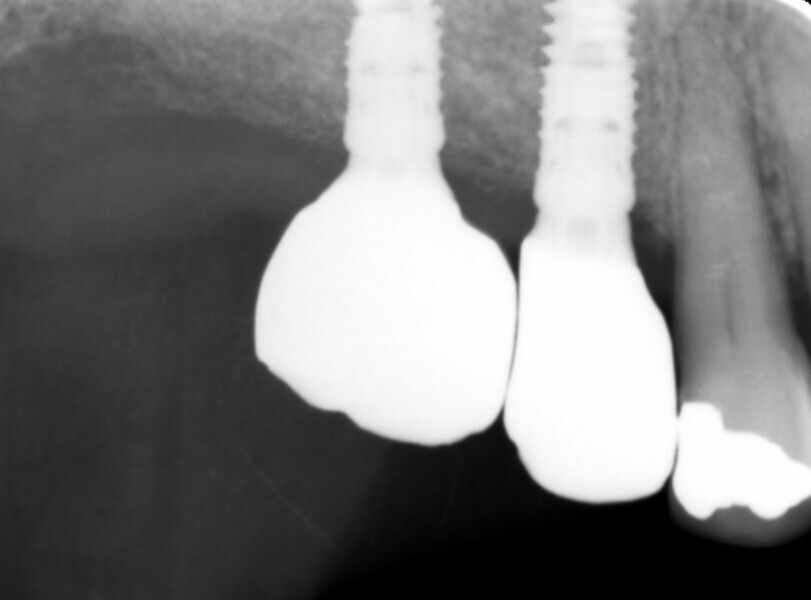

Fig. 2: Pre-op radiographic assessment.

A 64-year-old female patient presented to our practice with a heavily restored dentition. Her failing maxillary right first molar and second premolar had been extracted by her general dental practitioner (Fig. 1), leaving an unbounded edentulous area. Radiographic assessment indicated that there was ample bone depth in the posterior maxilla to allow for satisfactory implant placement (Fig. 2). An implant solution was provided using two individual screw-retained crowns supported by two OmniTaper EV implants (Dentsply Sirona) and using a digital workflow with Primescan and Atlantis (Dentsply Sirona).

Fig. 11: Post-op radiograph of the implants.

Fig. 16: Radiograph to verify correct seating of the restorations.